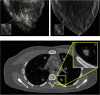

The accelerating complexity and variety of medical imaging devices and methods have outpaced the ability to evaluate and optimize their design and clinical use. This is a significant and increasing challenge for both scientific investigations and clinical applications. Evaluations would ideally be done using clinical imaging trials. These experiments, however, are often not practical due to ethical limitations, expense, time requirements, or lack of ground truth. Virtual clinical trials (VCTs) (also known as in silico imaging trials or virtual imaging trials) offer an alternative means to efficiently evaluate medical imaging technologies virtually. They do so by simulating the patients, imaging systems, and interpreters. The field of VCTs has been constantly advanced over the past decades in multiple areas. We summarize the major developments and current status of the field of VCTs in medical imaging. We review the core components of a VCT: computational phantoms, simulators of different imaging modalities, and interpretation models. We also highlight some of the applications of VCTs across various imaging modalities.